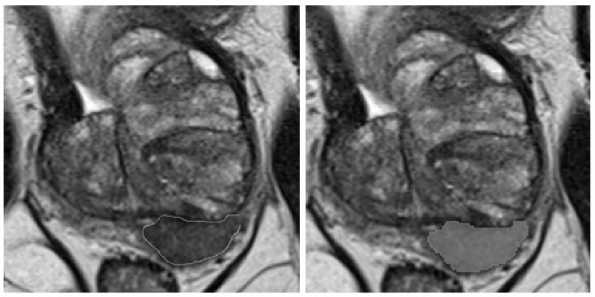

Вторым этапом осуществлялась тестовая разметка двумя врачами-рентгенологами с опытом работы в урогенитальной лучевой диагностике 3 и 4 года (разметчик 1 и разметчик 2). Для разметки применялось расширение mpReview в программном обеспечении 3D Slicer. Врачи-рентгенологи независимо друг от друга, а также без предварительного ознакомления с консенсусной разметкой, выполнили оконтуривание очагов, соответствующих критериям PI-RADS 3, 4, 5, используя контурную кисть (инструмент Draw) (Рис. 1) и обычную кисть (инструмент Paint) в виде круга (region of interest – ROI) и сферы (volume of interest – VOI). Используя инструмент Paint в виде круга (ROI), рентгенолог закрашивал зону интереса на одном срезе или нескольких срезах поочередно (Рис. 2). При применении инструмента Paint в виде сферы (VOI) (Рис. 3) разметчик выбирал необходимый диаметр и выделял область интереса (Рис. 3), то есть часть очага с визуально наиболее выраженными изменениями. Если очаг имел неправильную или овоидную форму, диаметр сферы выбирался исходя из наибольшего поперечного размера очага во избежание включения окружающих неизмененных тканей в маску. В тех случаях, когда диаметр сферы был равен толщине среза, в связи с техническими ограничениями VOI заменялся ROI. На примере используемого в нашем исследовании набора данных с указанной толщиной среза (Табл. 1) пограничным диаметром сферы являлся 8 миллиметров. При наличии нескольких патологических очагов в одном исследовании сегментация очагов производилась в соответствии с референсными изображениями и осуществлялась поочередно, начиная с правой доли простаты и продвигаясь сверху вниз. Такой порядок сегментации способствовал исключению несоответствий в масках конкретного очага между двумя экспертами в случаях мультицентрических форм. Результирующая маска и серии изображений (Т2-ВИ, ДВИ, ИКД) сохранялись в формате NIfTI (.nii). Время оконтуривания очага каждым методом разметки измерялось при помощи макроса Microsoft Excel оригинальной разработки. При нажатии кнопок «Старт» и «Финиш» фиксировалось текущее время рабочей станции; время разметки вычислялось как арифметическая разница между двумя нажатиями.

Рис. 3. Обычная кисть в виде сферы (VOI). Для создания маски очага разметчик выбирал инструмент Paint в виде сферы (VOI) и выделял область интереса.